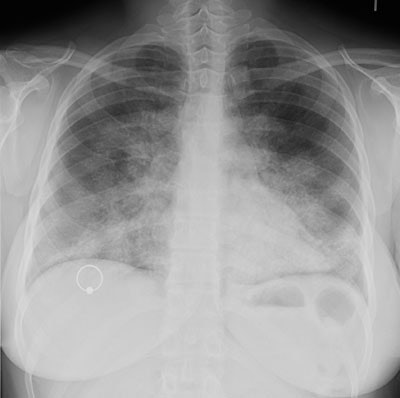

Alveolar Proteinosis

The CXR below demonstrates the characteristic findings in this disorder. There are confluence areas of alveolar consolidation in a "bat-wing" configuration which mimics pulmonary edema, although the heart size is normal and pleural effusions are absent.

Click image for larger view